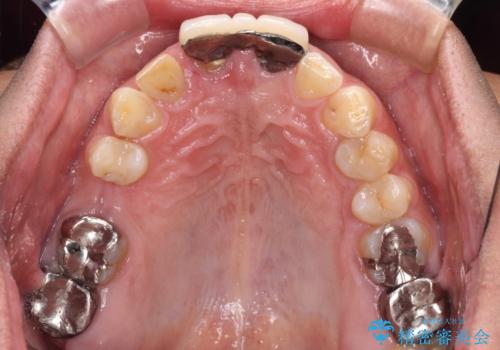

- 前歯の違和感と不自然な形態のブリッジを気にして来院された患者様です。

検査したところ、右前歯は抜歯が必要であったので、ブリッジを新製することとしました。

抜歯をすると歯肉が窪んでしまうので、傷口の治りを待って、歯肉移植を行うこととしました。

1歯は根管治療を行うことが必要と判断されたため、根管治療を実施することとしました。

歯肉移植や根管治療終了後、オールセラミッククラウンおよびブリッジにて補綴することとしました。